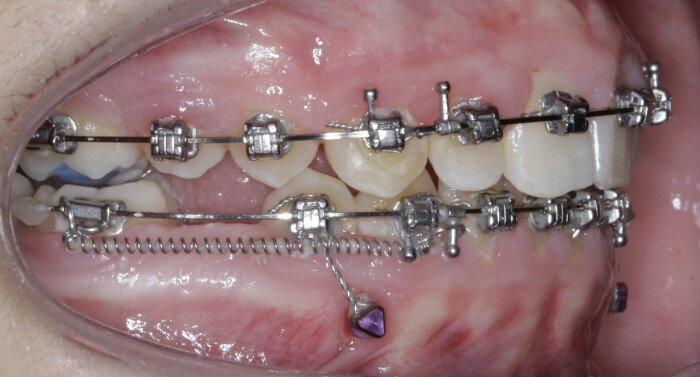

TADs are placed at the second visit with a 14 × 25 mm copper (Cu) and nickel–titanium (NiTi) wire and are tied from the anchor to the wire with an elastic thread (surgical thread; Fig. 6). Once the patient has progressed to larger Cu–NiTi wires and stainless steel, the TADs are tied to the wire using a power chain looped to the wire, or NiTi closing springs, depending on the thickness of the tissue (Figs. 7 & 8).

The same protocol is used, in which TADs are placed at the second visit with the 14 × 25 mm Cu–NiTi wire and tied to the archwire using elastic thread. Once in larger Cu–NiTi and stainless-steel wires, the TADs are tied to the wire using a power chain or NiTi closing springs (Figs. 17 & 18).